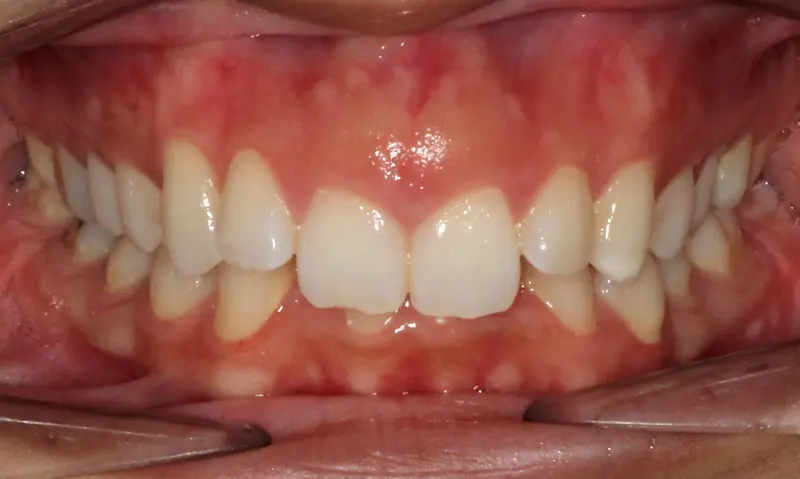

The Diagnosis

Severe crowding with blocked-out permanent teeth. The jaw size was insufficient to accommodate the erupting adult teeth, leading to significant rotation and displacement.

The Engineering

By intervening early, we utilized rapid palatal expansion to develop the arch width. This created the necessary space for the permanent teeth to erupt naturally, avoiding the need for future extractions.